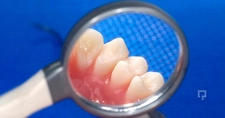

Diş Ekimi SüreciDiş ekimi süreci, genellikle birkaç aşamadan oluşur:

Diş ekimi, günümüzde oldukça yaygın bir işlem olmasına rağmen, her cerrahi müdahalede olduğu gibi bazı riskleri de beraberinde getirebilir. Enfeksiyon ve vücut reddi, bu işlemin potansiyel komplikasyonları arasında yer alır. Ancak, bu riskler uygun önlemlerle önemli ölçüde azaltılabilir.